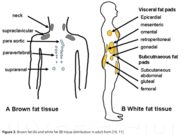

| 12:09, 23 ноября 2015 | Brown adipose tissue4.jpg (файл) |  |

74 КБ | Nico | Бурый жир | 1 |

| 12:07, 23 ноября 2015 | Brown adipose tissue3.jpg (файл) |  |

40 КБ | Nico | Бурый жир | 1 |

| 12:07, 23 ноября 2015 | Brown adipose tissue2.png (файл) |  |

44 КБ | Nico | Бурый жир | 1 |

| 14:13, 22 ноября 2015 | Brown adipose tissue1.png (файл) |  |

96 КБ | Nico | Бурый жир | 1 |